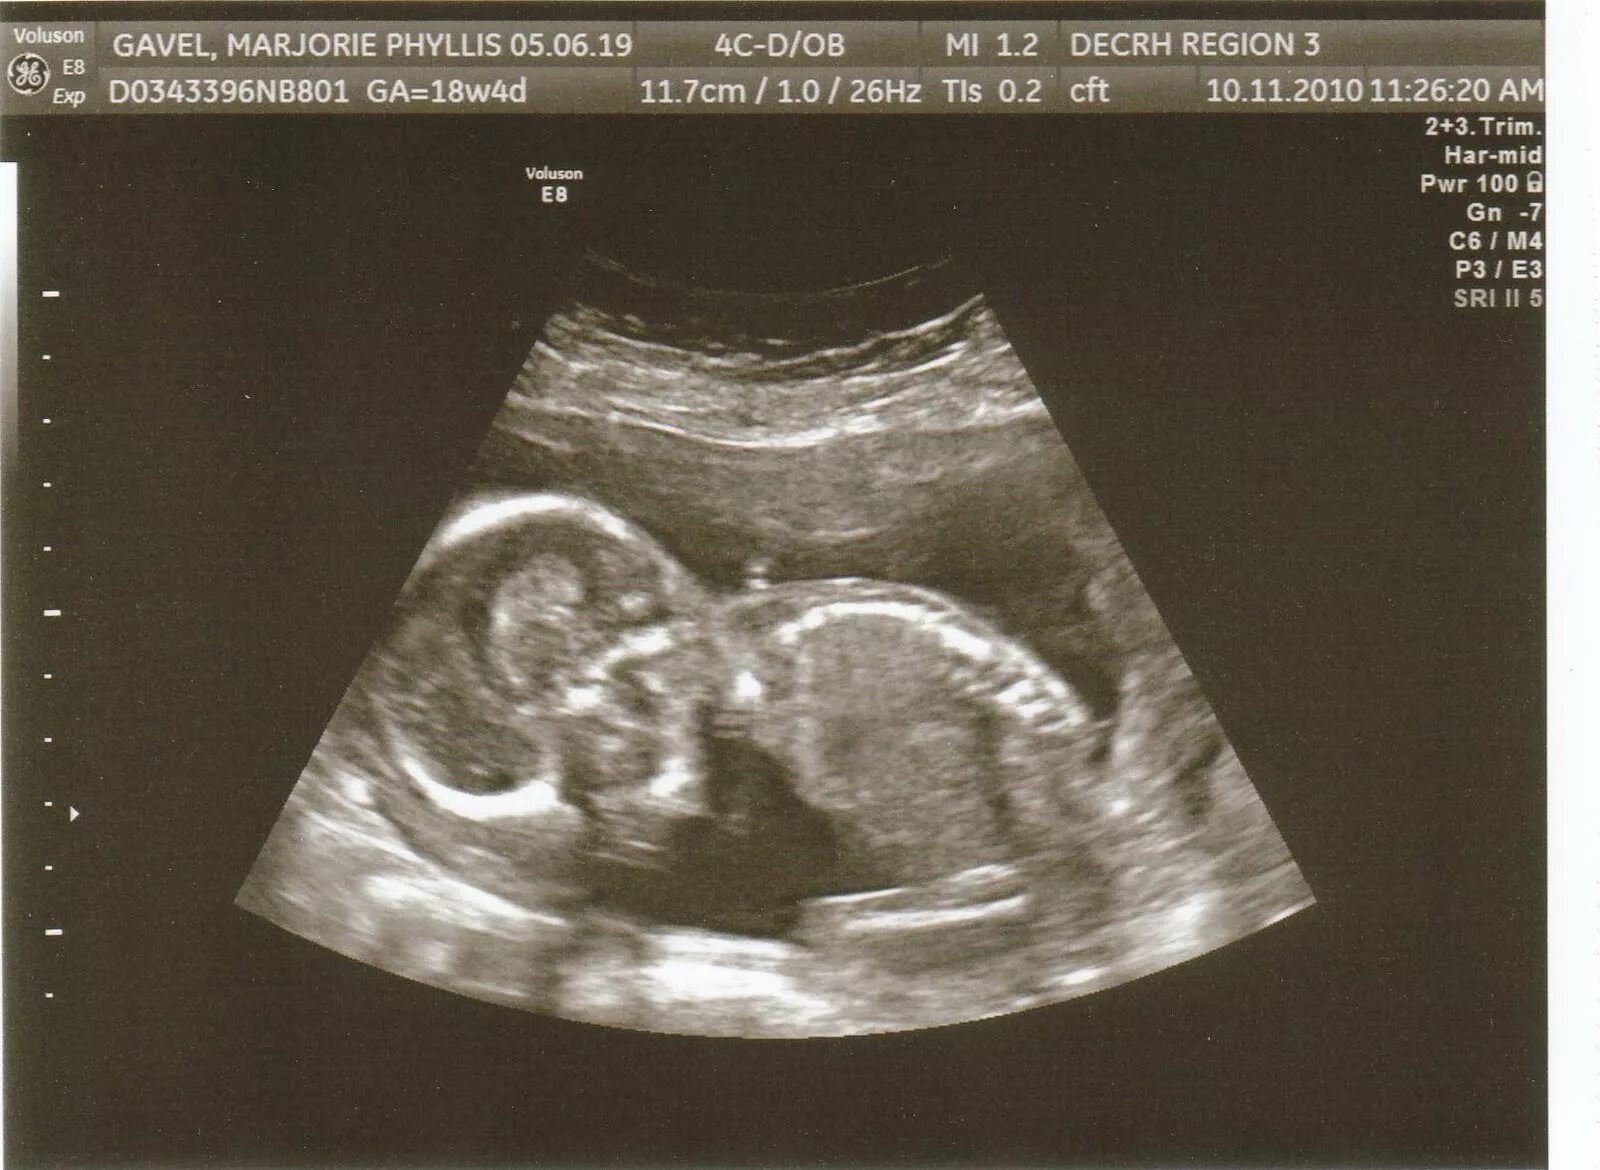

18 недель как выглядит малыш